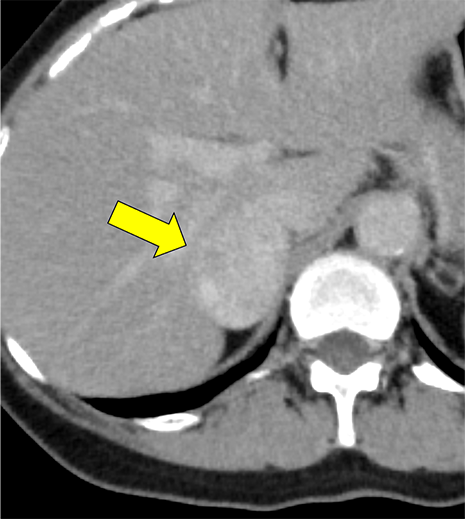

本例は、偶発的に指摘された右副腎腫瘍である。高血圧はあるが内服せず経過観察されている患者で、1cm/5年程度の非常に緩徐な増大を示す多血性の腫瘍を認める。腫瘍はI-123MIBGシンチ陰性であり、内分泌内科での精査においてもホルモン産生を疑う所見に乏しく、褐色細胞腫よりも海綿状血管腫が疑われていた。しかし、増大傾向があり破裂や出血のリスクなども考慮されて手術の方針となった。手術中に血圧の変動を認め、病理で褐色細胞腫の診断となった。

褐色細胞腫は副腎髄質に存在するクロム親和性細胞に由来する腫瘍で、カテコールアミンなど種々の生理活性物質を産生する。ダイナミック造影で動脈相での強い濃染と持続する造影効果が特徴とされ、サイズが大きい病変は嚢胞変性や出血、壊死を伴うことが多い。かつては、臨床的に褐色細胞腫が疑われる場合、ヨード造影剤の投与はカテコールアミンの過剰放出を誘発し、高血圧クリーゼを引き起こす可能性があるため原則禁忌とされていた。しかし、現在汎用されている非イオン性・低浸透圧性造影剤であればこの現象は起こらないとの報告もあり、European Society of Urogenital Radiology Guidelines on Contrast Media, ver 10.0では、「経静脈的ヨード造影剤の投与をする場合でも特別な準備の必要はない」と記載されている。イオプロミドの電子添文上は、禁忌にはなっていないものの、「慎重に投与すること」との記載になっている。本例では、血管腫疑いとして合計5回の造影CTが行われているが、血圧変動や頭痛、動悸などの症状は一度も認められなかった。

本例の画像所見として、褐色細胞腫としてダイナミック造影の濃染パターンは典型的ともいえたが、大きさの割に変性が乏しい点、MIBGシンチでの核種集積に乏しい点、ホルモン産生に乏しい点など非典型的な要素が複数存在し、海綿状血管腫を除外しきれなかった。なお、褐色細胞腫はRET遺伝子変異による多発性内分泌腺腫症(multiple endocrine neoplasia;MEN)type 2A・2B、VHL遺伝子によるvon Hippel-Lindau病、NF1遺伝子による神経線維腫症1型に生じることが知られているが、これらの疾患を想起させるような他病変は本例には見つかっていない。

腺腫や骨髄脂肪腫など良性と断定できない副腎腫瘍の鑑別をする際、大きい病変であれば褐色細胞腫や副腎癌、悪性リンパ腫などが考慮される。核医学検査も有用ではあるが、本例のように偽陰性となることも稀にあり、その際はダイナミック造影パターン、血管への浸潤、転移の有無などから判断しなければならない。適切なタイミングで撮像されたダイナミック造影CTは、多血性病変であるかの評価、周囲の血管との関係性、多血性の転移巣の有無などの判断に寄与し、診断の重要な手がかりとなると考える。